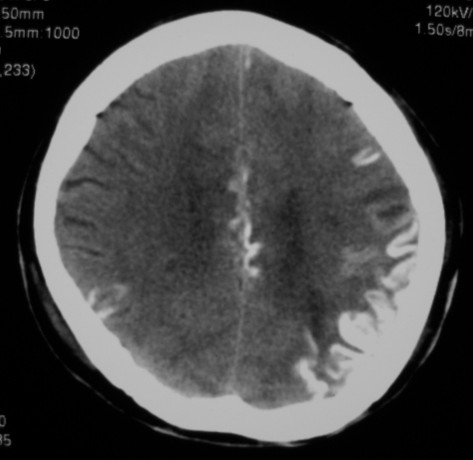

第一次ct片脑出血术后,出血吸收期。第二次ct 片左颞顶枕部及右颞顶部有脑回样高密度影。考虑珠网膜下腔出血。脑出血术后改变,脑出血恢复期 并脑积水。

两次的片都有,第二次比第一次的明显